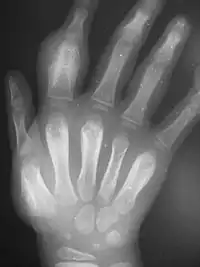

| Nodules on the elbow resulting from a Treponema pallidum pertenue bacterial infection | |

Secondary yaws affects the skin and bones.[13] The most common bone-related problem is periostitis, an inflammation around the bone, often occurs in the bones of the fingers and the long bones of the lower arms and legs, causing swollen fingers and limbs.[13] This causes pain at night and thickening of the affected bones (periostitis).[2] About 75% of infected children surveyed in Papua New Guinea reported joint pain.[2] Swollen lymph nodes, fever, and malaise are also common.[13]

Tertiary yaws can include gummatous nodules. It most commonly affects the skin. The skin of the palms and soles may thicken (hyperkeratosis). Nodules ulcerating near joints can cause tissue death. Periostitis can be much more severe. The shinbones may become bowed (saber shin)[13] from chronic periostitis.[2]